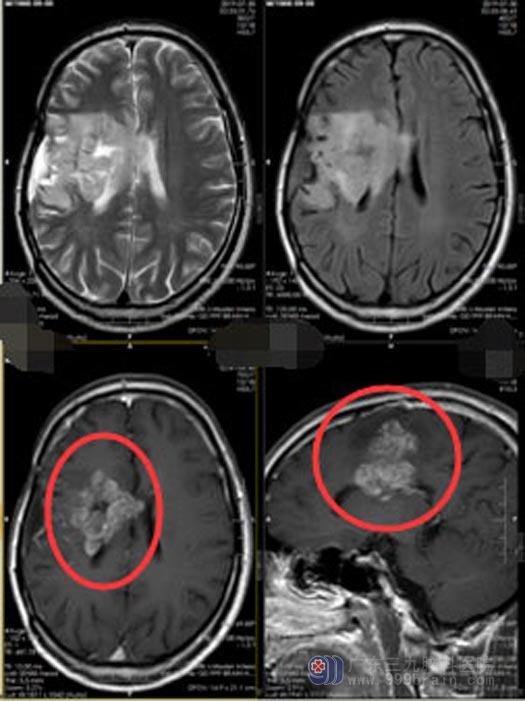

李叔,七年前由于胶质瘤复发在广东三九脑科医院神经外五科就诊,头颅MR检查示:右额顶叶病变,直径约5cm,行“右额顶叶肿瘤切除术”,病理结果:少突星型细胞瘤(WHOⅡ级),术后左侧肢体乏力减轻,无四肢抽搐,语言流利,之后一直在行放化疗。

最近因为左侧肢体突然抽搐且肌力明显下降,再次来到神经外五科。MR结果示:右额颞岛叶,右侧基底节,丘脑,放射冠,胼胝体体部占位性病变,强化范围较前明显增大,范围约5.7cm×5.5cm×2.7cm,考虑肿瘤再次复发。

▲手术前